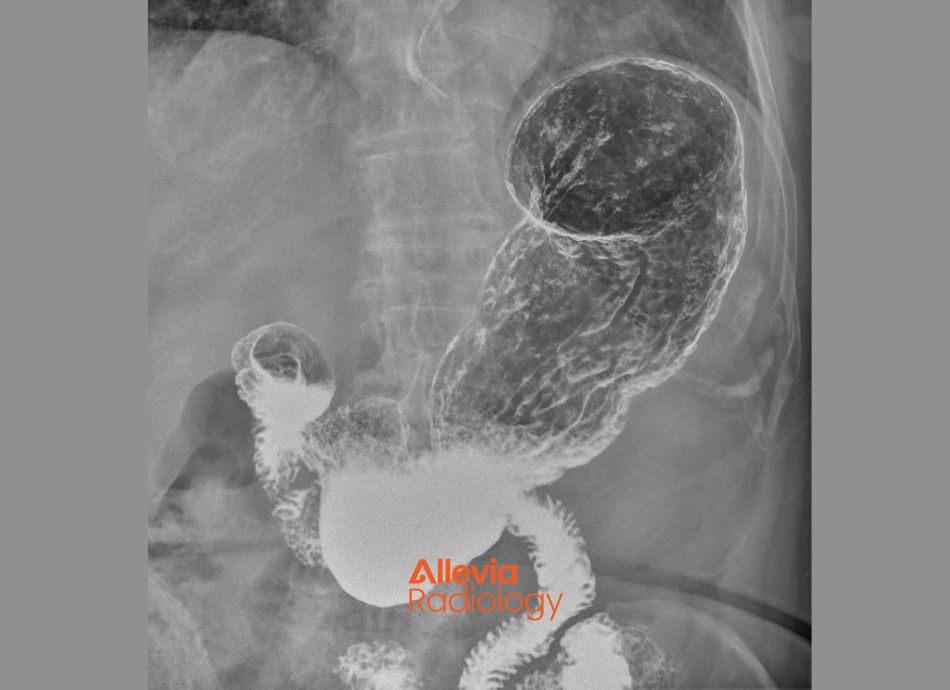

Barium swallow

– done to check for problems in your throat, oesophagus, stomach and parts of your small intestine. You swallow a drink containing barium (known as a ‘contrast’) which shows up on the fluoroscopy images. Read more about barium swallow and barium enema (occasionally done to look at the lower part of your bowel).

The image below is of a barium swallow.

X-ray image of a barium swallow in the oesophagus

Image credit: Canva